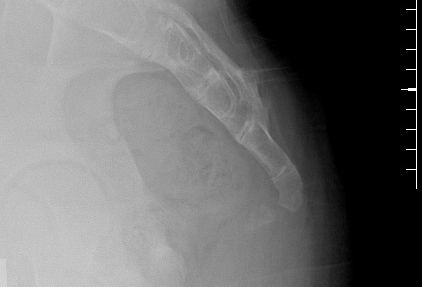

Lateral sacrococcygeal x-ray in a patient with post-traumatic chronic coccygodynia, showing sacrococcygeal synostosis (fusion, normal variant) and Co1-Co2 anterior subluxation

From the personal collection of Dr R. Schrot